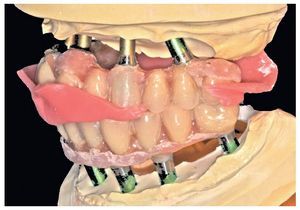

Pese a ello, es importante someter las estructuras a un control visual y mecánico, a fin de corregir eventuales discrepancias menores (figs. 99 a 102). A continuación se procede al montaje utilizando dientes protésicos prefabricados de composite (SR Phonares NHC, Ivoclar Vivadent, Ellwangen, Alemania), los cuales reproducen el tipo funcional correspondiente en virtud de sus propiedades morfológicas y estructurales y se integran armoniosamente en cuanto a su longitud dental (figs. 103 a 105). Durante la comprobación de las restauraciones protésicas, se evalúan clínica y radiológicamente ante todo la pasividad y la precisión del ajuste de la estructura. Acto seguido se lleva a cabo una comprobación de la oclusión y de la dimensión vertical, del estado de las prótesis y del tejido blando en la cresta alveolar, así como la verificación del espacio libre lingual, incluida la fonación, y el apoyo de los labios y las mejillas (figs. 106 y 107). También se debe comprobar la facilidad de higiene de la restauración de acuerdo con las habilidades manuales del paciente. A continuación se debe verificar la posición tridimensional de los dientes anteriores con los labios cerrados y durante la sonrisa, así como el aspecto global de la rehabilitación protésica.

Durante la fase de laboratorio final pueden ser necesarios diversos ajustes estéticos y funcionales. A continuación puede confeccionarse la restauración definitiva (figs. 108 a 111). Posteriormente se procede al control final mediante sendos montajes cruzados de la restauración definitiva y del modelo de planificación (figs. 112 a 115).

Figs. 108 a 111. Vista frontal y lateral de los puentes implantosoportados terminados.

Para la rehabilitación definitiva del paciente (figs. 116 a 124) deben comprobarse de nuevo todos los aspectos de la sesión anterior y debe procederse a la cementación de las prótesis. Son indispensables controles de seguimiento a corto plazo (al cabo de 1, 3 y 5 semanas) para el ajuste óptimo de la oclusión y la comprobación de la higiene oral con una prótesis que habitualmente ofrece aberturas de acceso periimplantares más estrechas que una prótesis provisional. Tres y seis meses después de la finalización del tratamiento se deben realizar controles clínicos, y una vez al año deberían llevarse a cabo sendos controles clínico y otro radiológico.

Figs. 116 y 117. Las restauraciones definitivas fijadas a los implantes. Cabe destacar la buena curación del tejido blando periimplantar.

Figs. 118 a 120. La situación intraoral final.